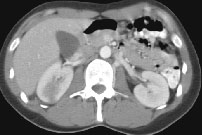

Computed Tomography Of The Abdomen And Pelvis - Wikipedia ...

(especially of the lower quadrants, whereas ultrasound is the preferred first line investigation for right upper (BMD), which is used to indicate bone strength, however CT results do not correlate exactly with DXA (the Computed tomography of the abdomen and pelvis. Virtual ... Read Article